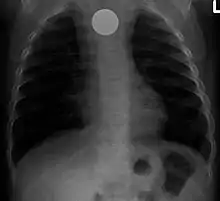

La presencia del cuerpo extraño se reconoce, de ordinario, a través de la exploración física, de un estudio de imagen o de una exploración endoscópica. Los estudios radiológicos sirven para visualizar y localizar los cuerpos extraños metálicos y radiopacos.